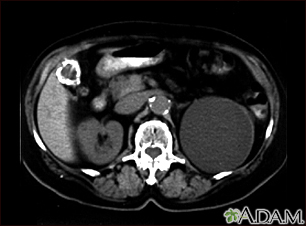

Kidney cyst with gallstones - CT scanBackKidney cyst with gallstones - CT scanA CT scan of the upper abdomen showing a fist-sized cyst of the left kidney and gallstones (the kidney cyst was found by chance; there were no symptoms). E-mail FormEmail ResultsName:Email address:Recipients Name:Recipients address:Message: